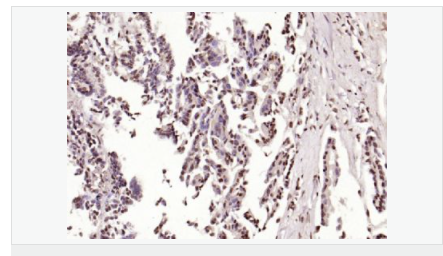

交叉反應(yīng):Human,Mouse,Rat(predicted:Dog,Pig,Rabbit,GuineaPig) 推薦應(yīng)用:IHC-P,IHC-F,ICC,IF,Flow-Cyt,ELISA

| 產(chǎn)品應(yīng)用 | ELISA=1:5000-10000 IHC-P=1:100-500 IHC-F=1:100-500 Flow-Cyt=1μg/Test ICC=1:100 IF=1:100-500 (石蠟切片需做抗原修復(fù)) not yet tested in other applications. optimal dilutions/concentrations should be determined by the end user. |